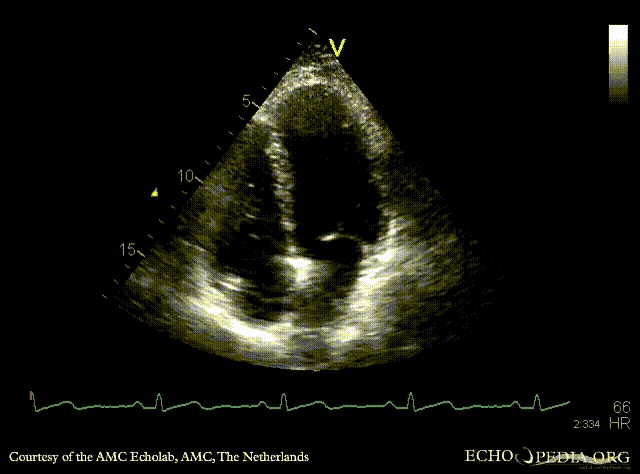

Contrast echocardiogram

AMC Echolab, AMC, The Netherlands

A4CH with contrast: right to the left shunt